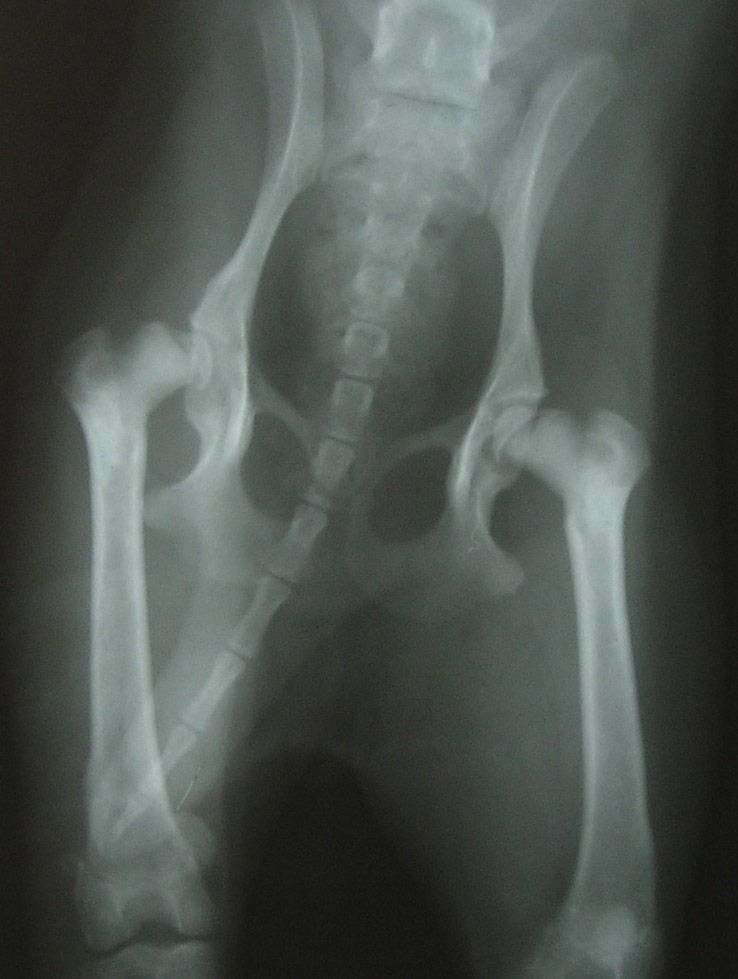

Artrodesis

Es una cirugía que consiste en fusionar articulaciones que tienen problemas de inestabilidad, dolor o artrosis, para eliminar el dolor y tener una buena funcionalidad y calidad de vida.

Se colocan placas especiales con tornillos, que adaptados a la forma que queremos que la articulación adopte una vez fusionada.